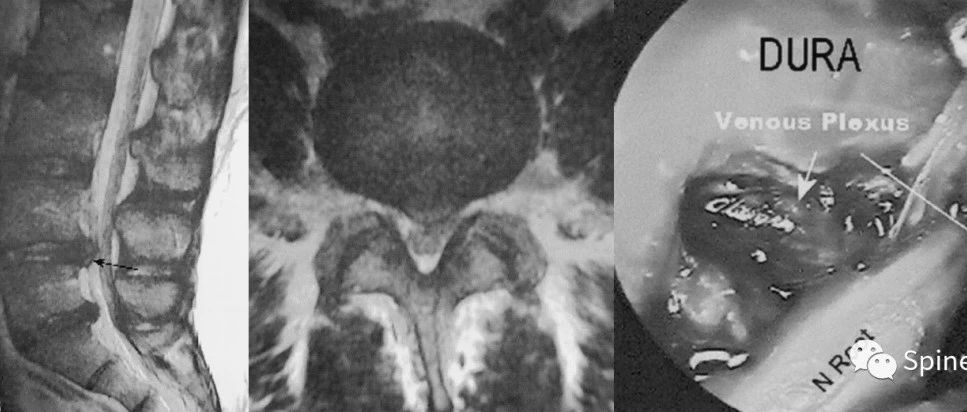

硬膜外静脉丛曲张(epidural varices)